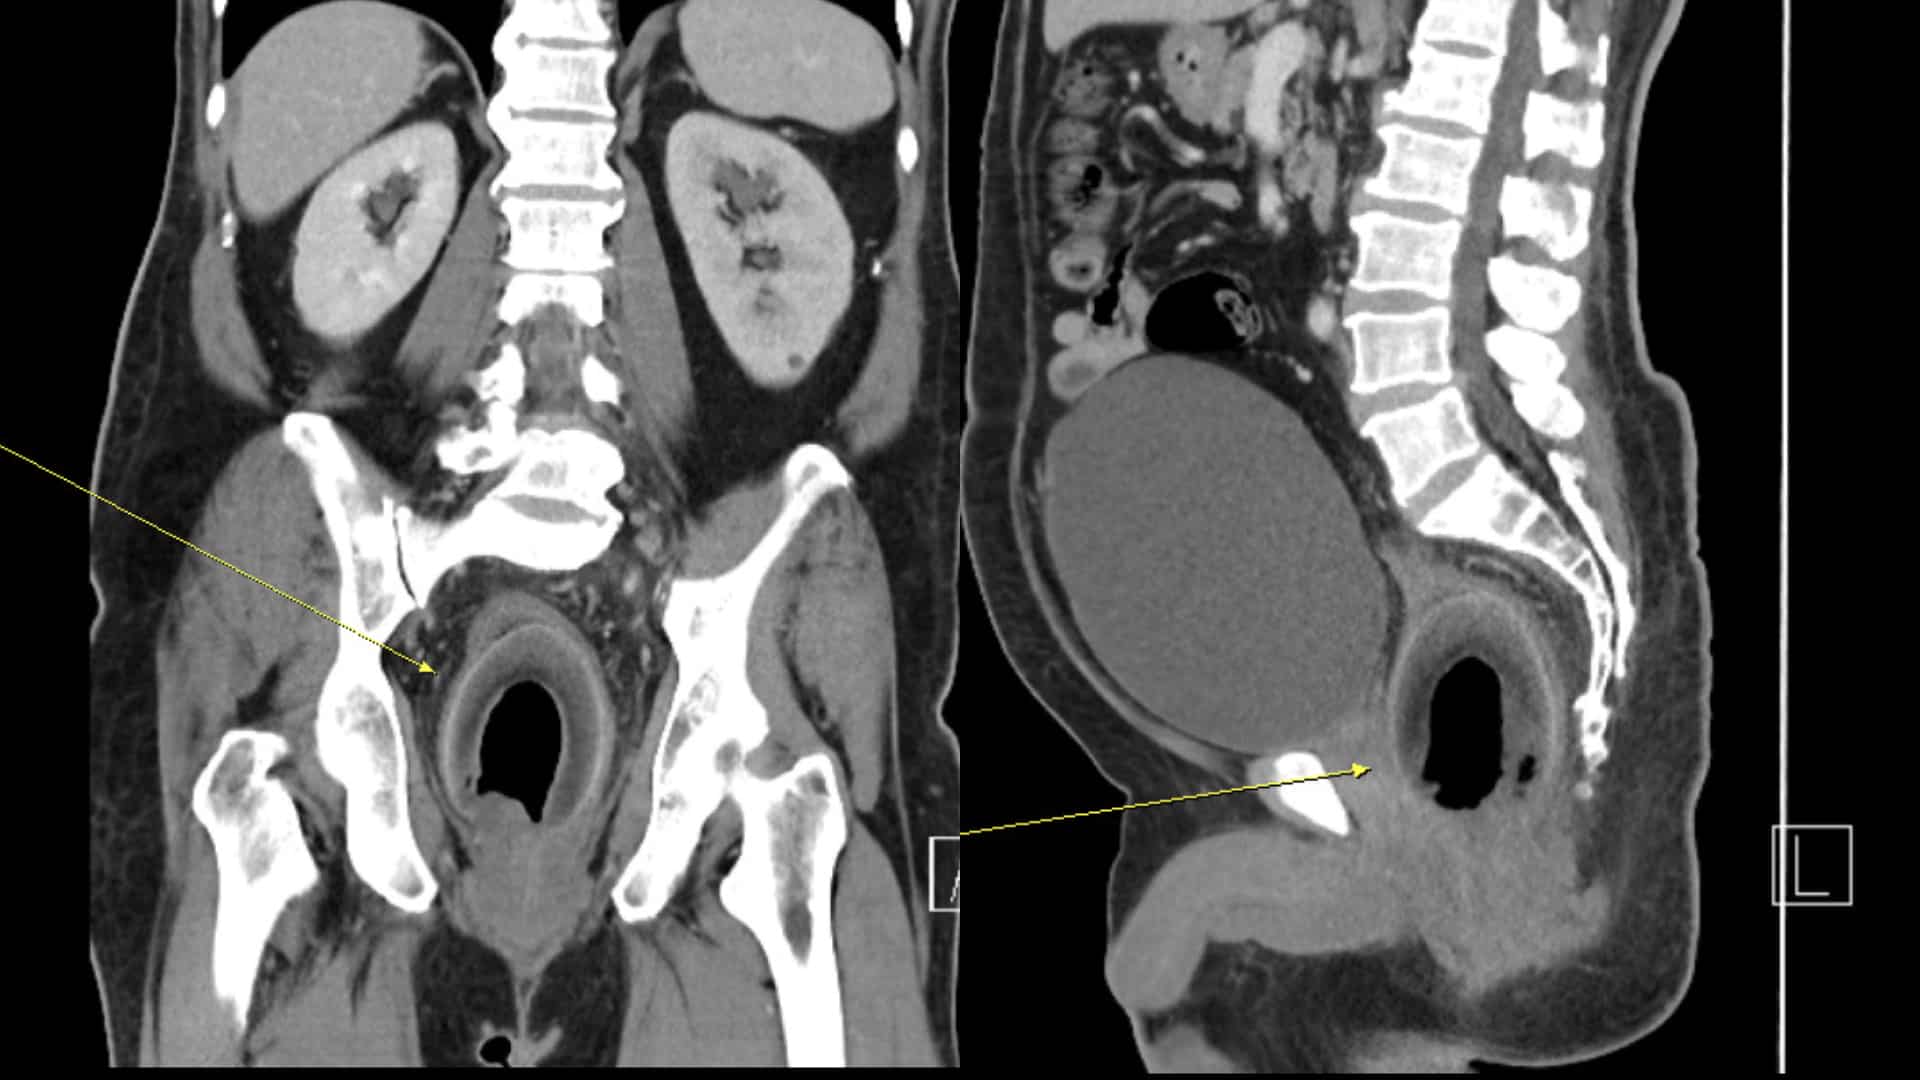

วันนี้ 20 มีนาคม 2567 ข่าวสุดแปลกนี้เกิดขึ้นที่เมืองเกาสง ประเทศไต้หวัน เมื่อชายวัย 50 กว่าปี ต้องไปโรงพยาบาลอีต้าด้วยอาการปวดท้องอย่างหนักและไม่สามารถปัสสาวะได้ เมื่อแพทย์ทำการ CT Scan ถึงกับผงะ เพราะพบว่ามี “มะพร้าวทั้งลูก” อยู่ในลำไส้ตรงของเขา แถมเจ้ามะพร้าวยังไปกดทับท่อปัสสาวะอีกด้วย

จากรายงานระบุว่าชายผู้นี้มีอาการปวดท้องมาก ปัสสาวะไม่ออก และท้องผูกอย่างหนักมา 2 วันแล้ว โดยไม่มีไข้ คลื่นไส้ หรืออาเจียน เมื่อแพทย์ตรวจร่างกายพบว่าท้องของเขามีอาการบวม กดแล้วเจ็บ แพทย์จึงสั่งทำ CT Scan และพบเข้ากับมะพร้าวในลำไส้ตรง ซึ่งจำเป็นต้องผ่าตัดด่วน! สุดท้ายมะพร้าวทั้งลูกขนาด 7.5 x 5.7 x 5.5 เซนติเมตร ก็ถูกเอาออกได้สำเร็จ

ภาพจาก: Yida Hospital